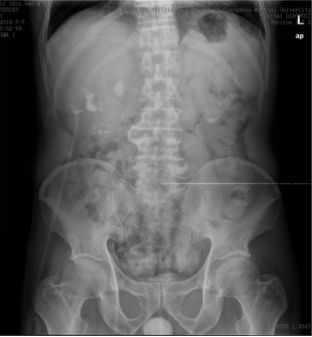

随后,李先生在经过5天恢复与治疗后,广医五院泌尿科专家再为其进行了右侧经皮肾碎石取石术,由于右侧的结石数量更多、面积更大,手术过程相对比较困难,但仍是尽了最大努力将患者的大部分结石清除。一周后,李先生康复出院,他对泌尿外科表示由衷的感谢。